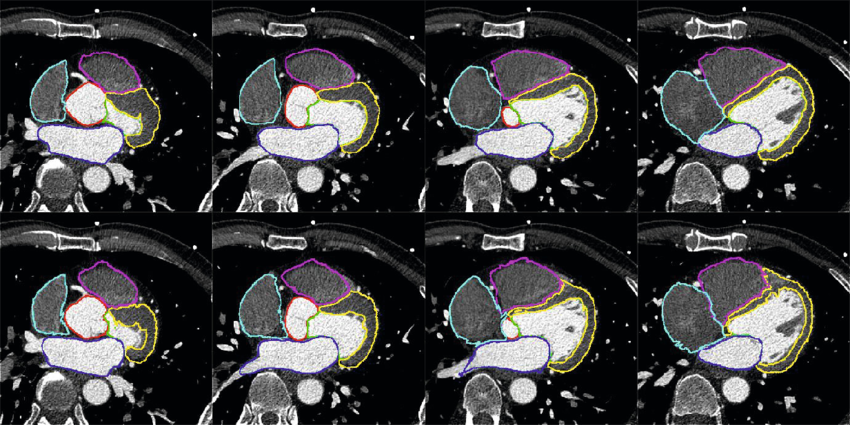

Myocardial segmentation using constrained multi-seeded region growing

Multi-slice short-axis acquisitions of the left ventricle are fundamental for estimating the volume and mass of the left ventricle in cardiac MRI scans. Manual segmentation of the myocardium in all time frames per each cross-section is a cumbersome task. Therefore, automatic myocardium segmentation methods are essential for cardiac functional analysis. Region growing has been proposed to segment the myocardium. Although the technique is simple and fast, non uniform intensity and low-contrast interfaces of the myocardium are major challenges of the technique that limit its use in myocardial